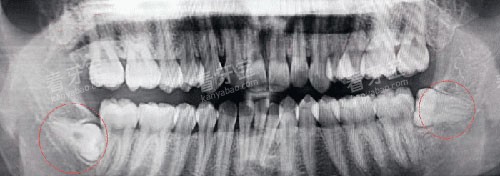

简单智齿(已萌出、位置正):优先选择社区医院。

复杂阻生齿(未萌出、靠近神经管):建议综合医院口腔颌面外科。

CBCT检查:300元(自费)。

提前询问医院是否可用普通X光片替代CBCT(费用约50元)。